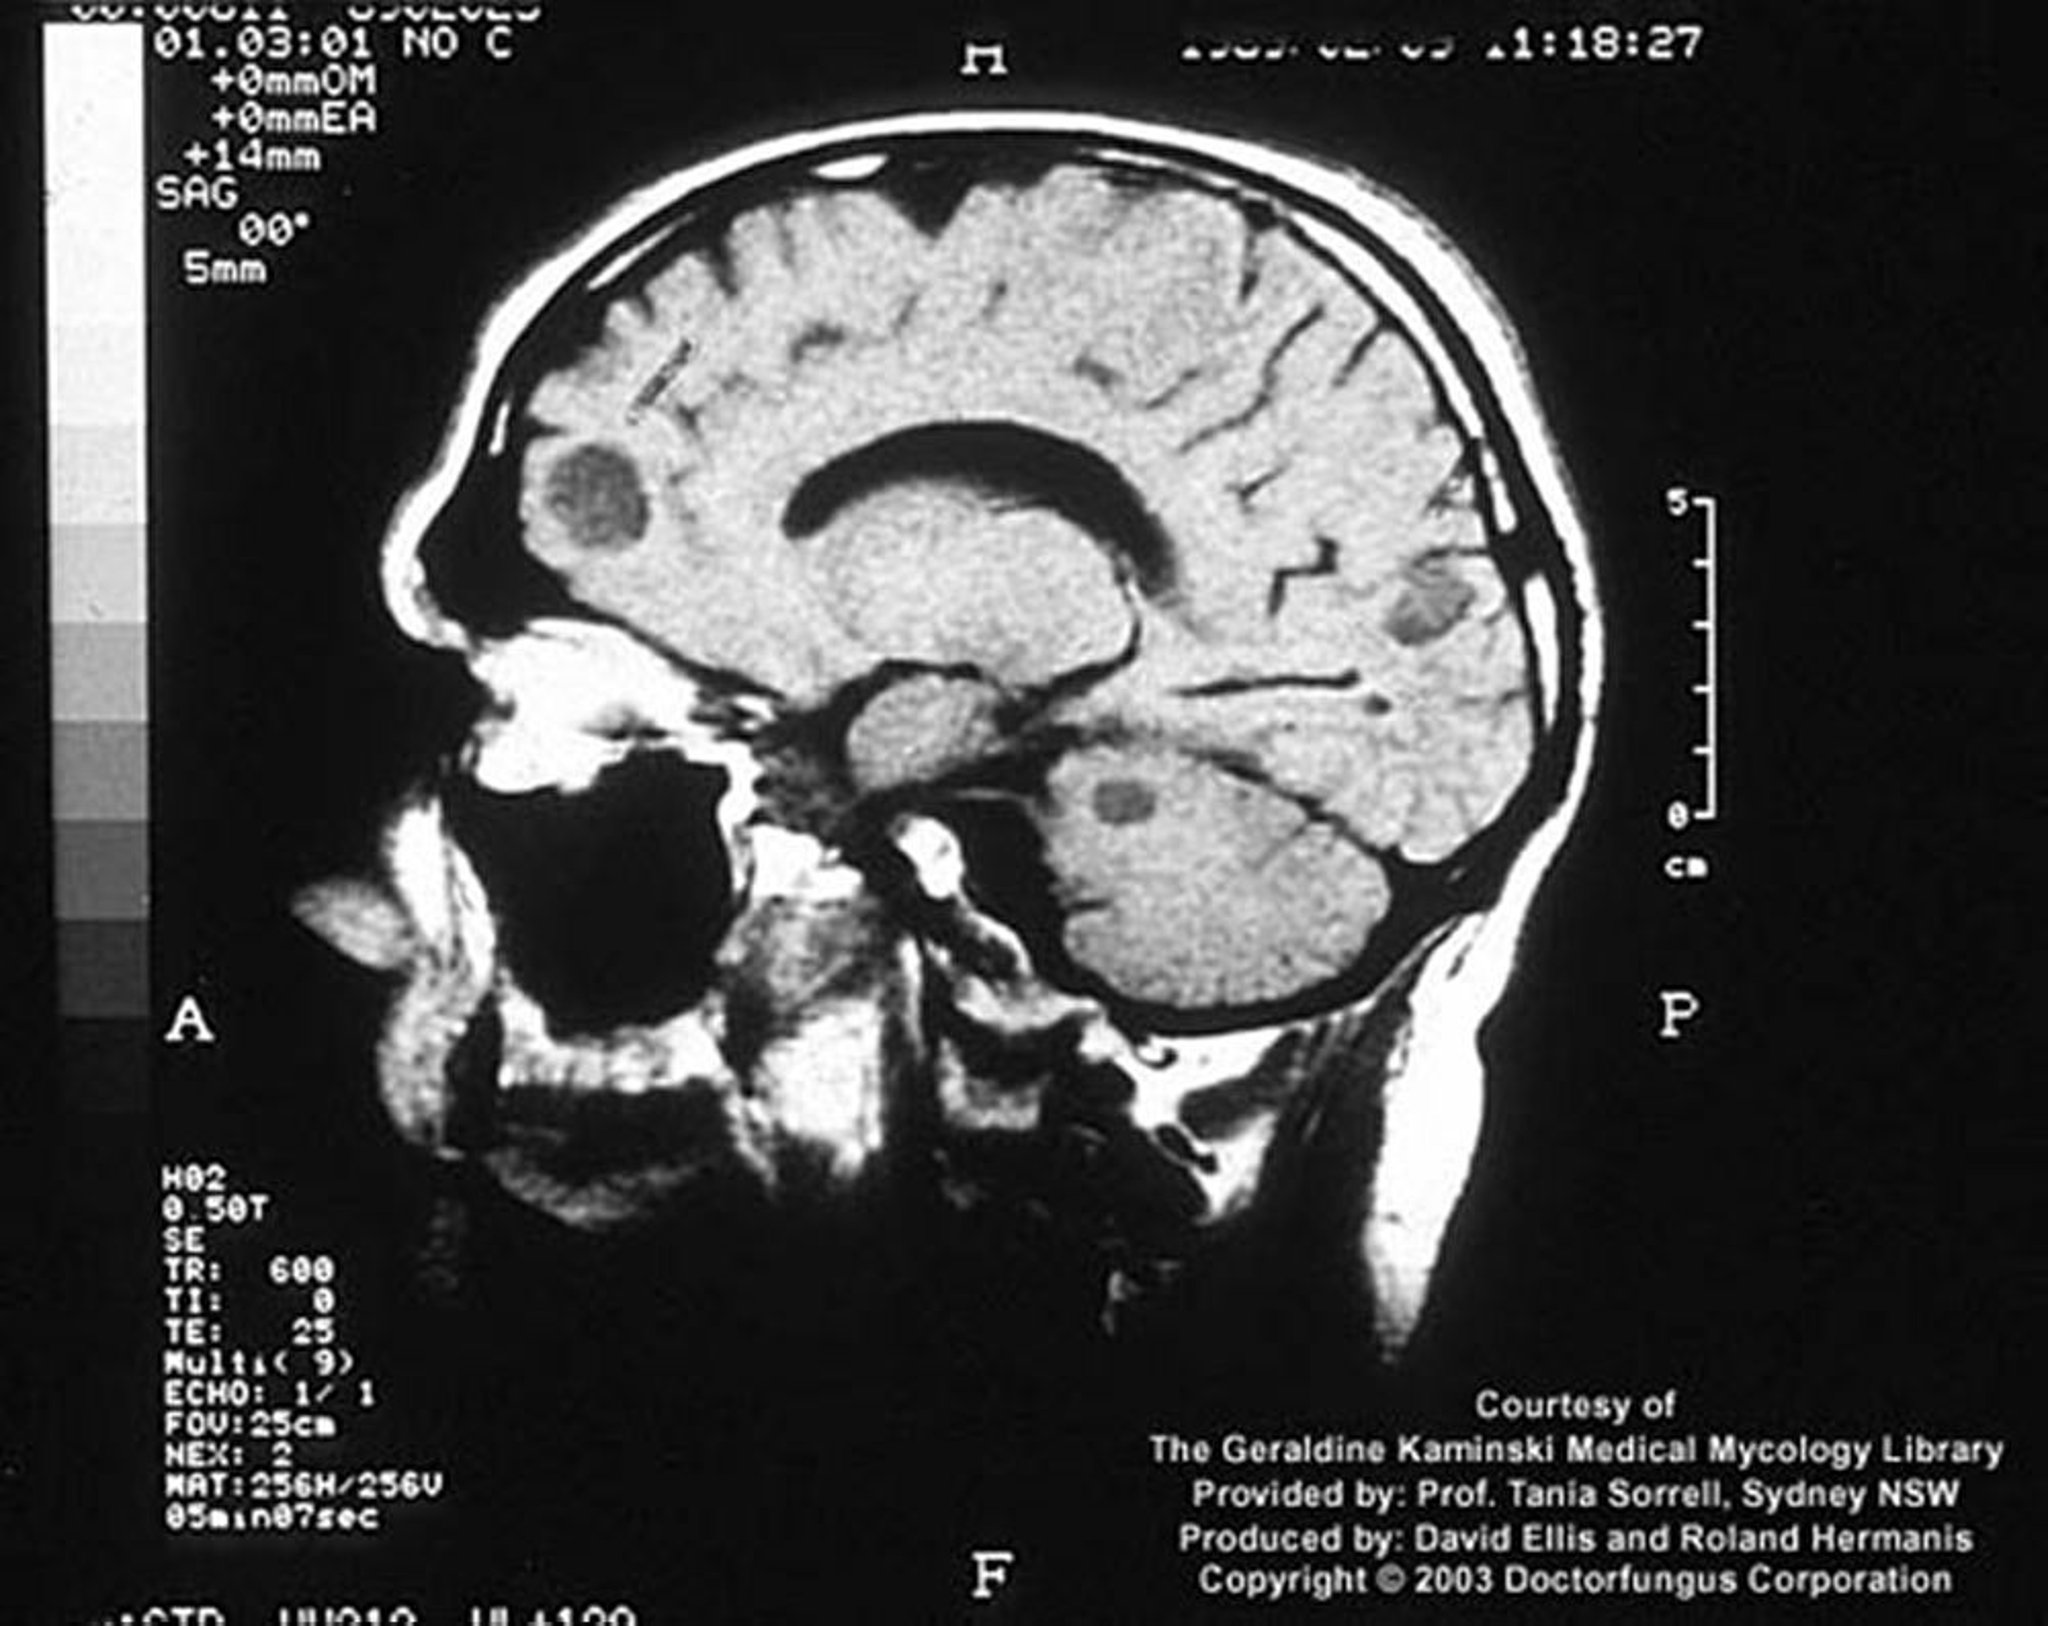

Criptococcosi (sistema nervoso centrale)

In un ospite immunosoppresso, l'infezione da criptococco può manifestarsi come lesioni cerebrali focali chiamate criptococcomi.

Image courtesy of www.doctorfungus.org © 2005.